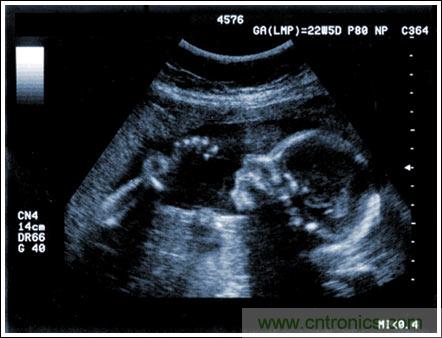

通過發(fā)射超聲能量進(jìn)入人體,接收并處理返回的反射信號,相控陣超聲系統(tǒng)可以生成體內(nèi)器官和結(jié)構(gòu)的圖像,映射血液流動和組織運(yùn)動,同時提供高準(zhǔn)確度的血流速度信息。傳統(tǒng)設(shè)計中,構(gòu)建這樣的成像系統(tǒng)需要大量的高性能相控陣發(fā)射器和接收器,使得車載設(shè)備體積龐大且價格昂貴。近年來,隨著集成工藝的進(jìn)步,設(shè)計人員能夠獲得小尺寸、低成本而且高度便攜的成像系統(tǒng)方案,并可達(dá)到接近大型成像設(shè)備的性能指標(biāo)。而新的設(shè)計挑戰(zhàn)依然存在,即在進(jìn)一步提高方案集成度的同時提高系統(tǒng)性能和診斷能力。